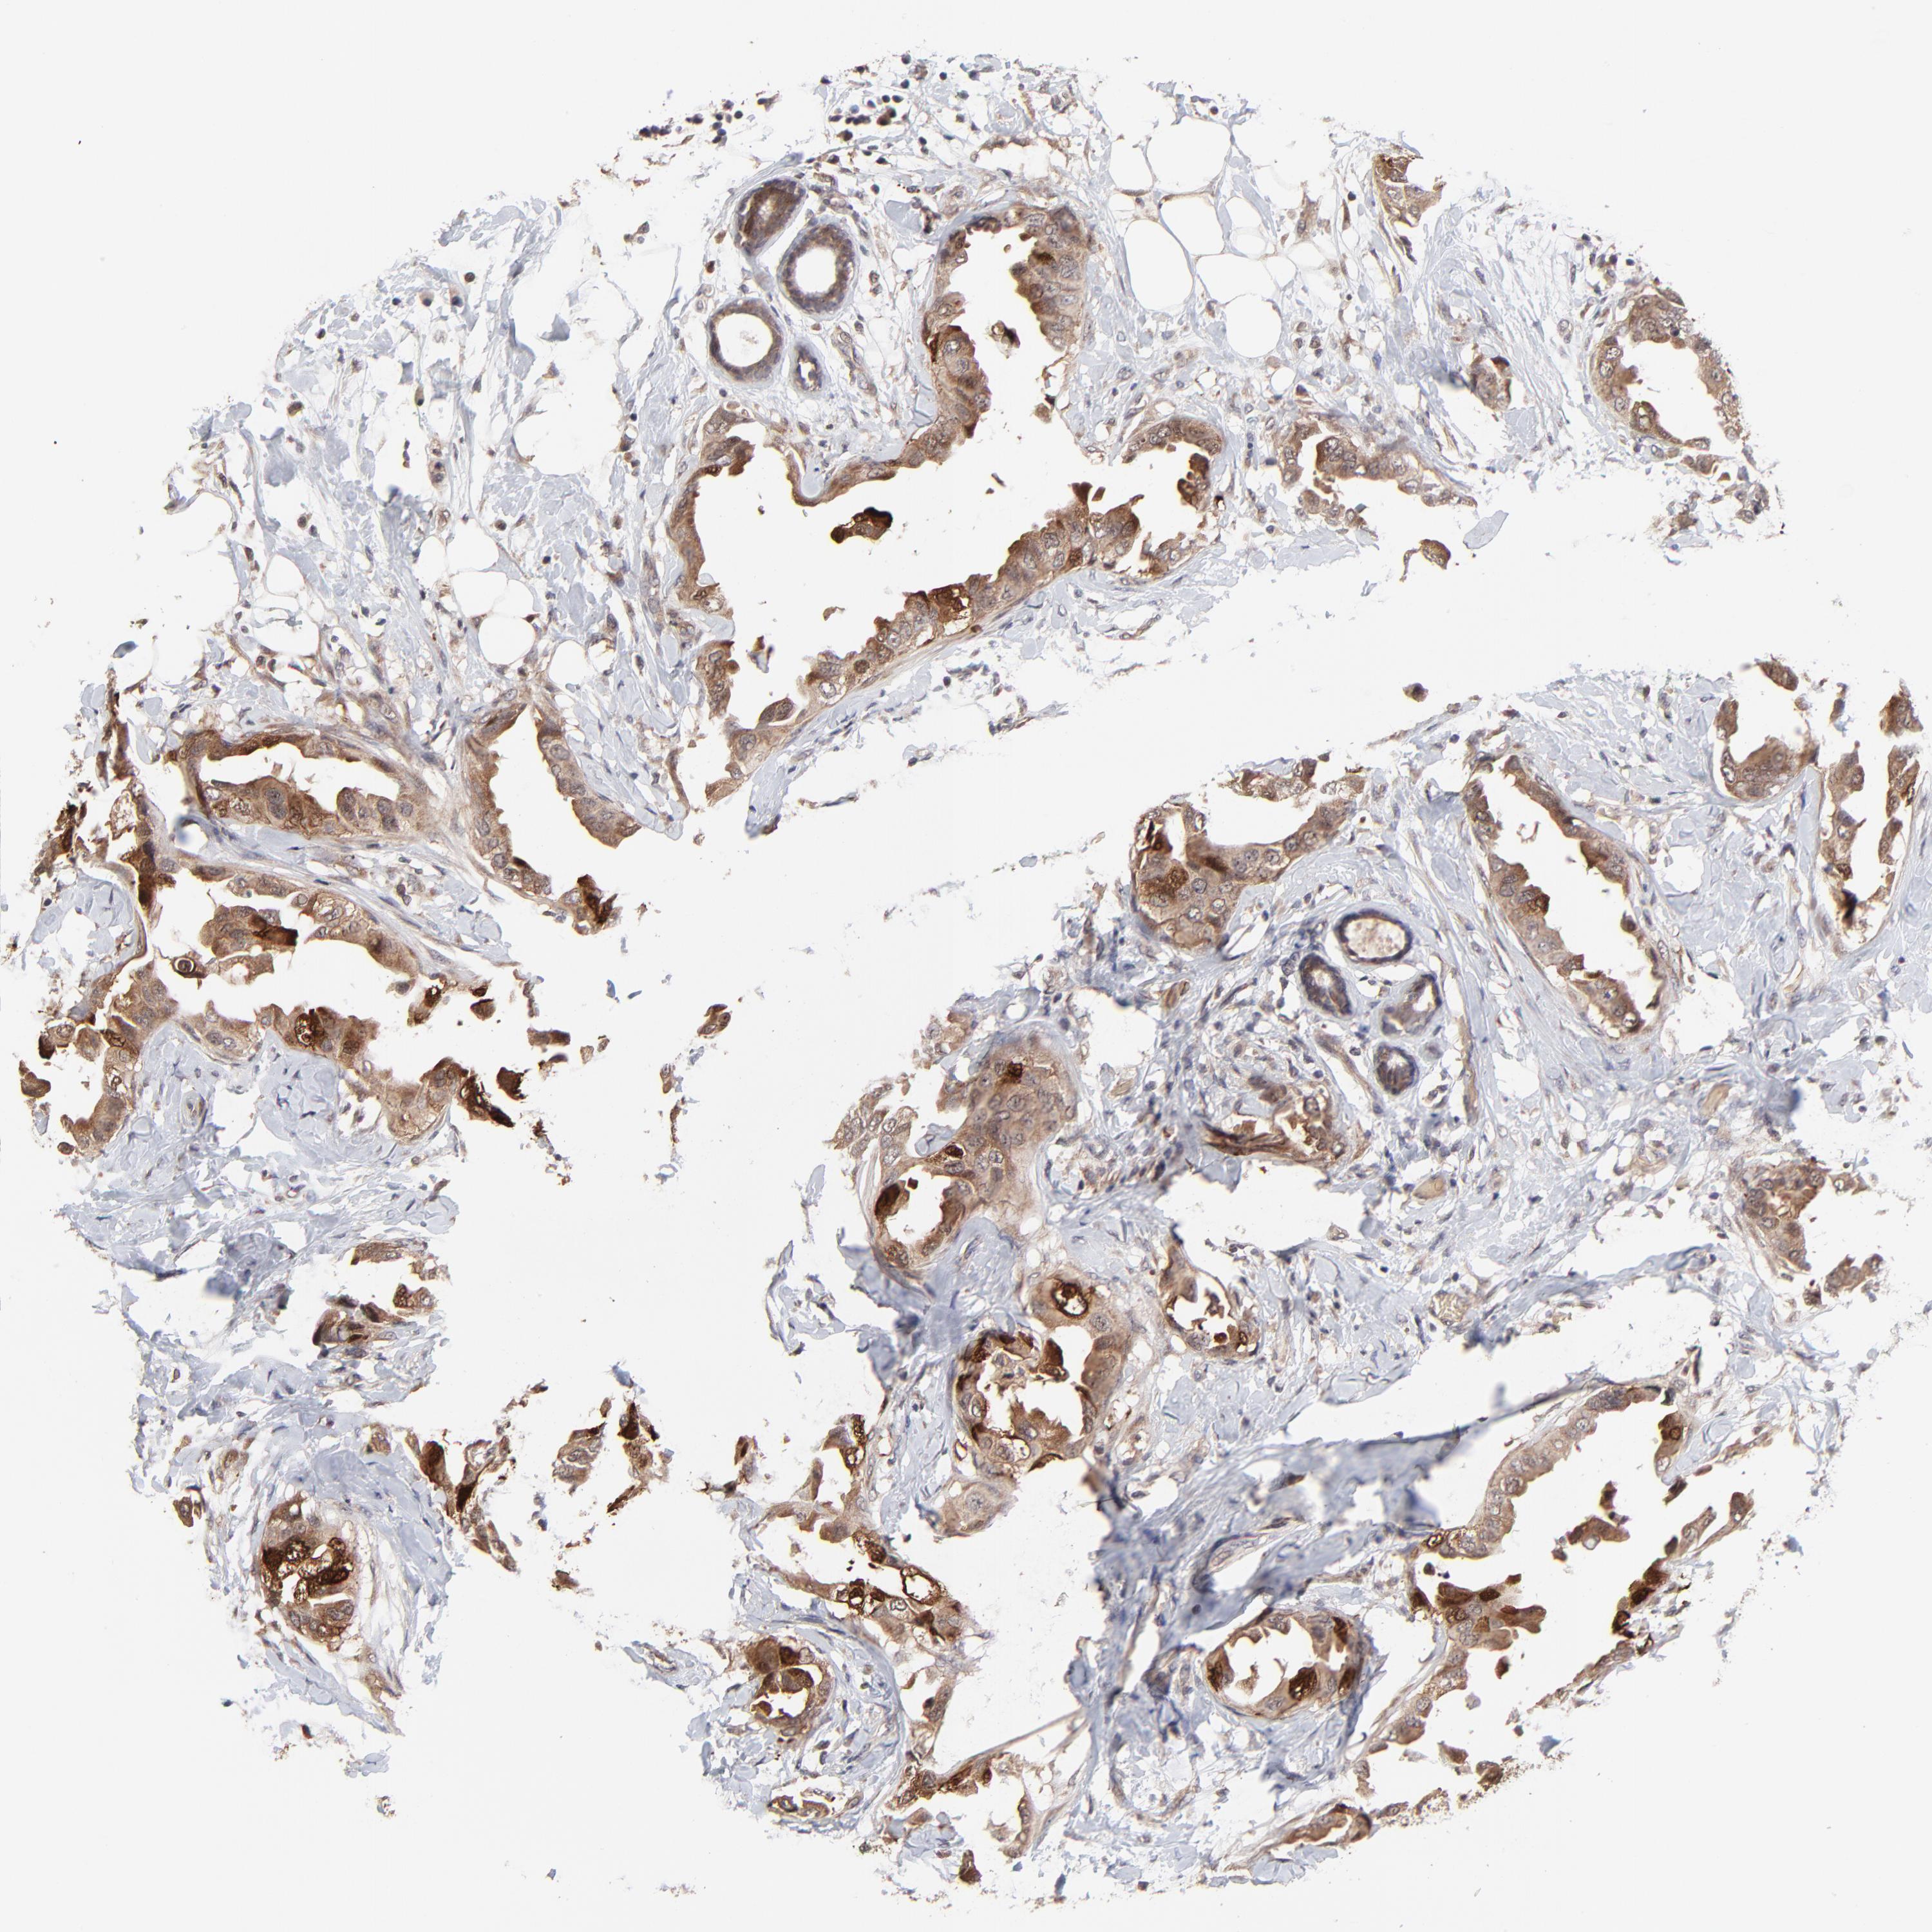

CANCER BREAST CANCER Show tissue menu

BRCA TCGA BRCA VALIDATION PROTEIN EXPRESSION